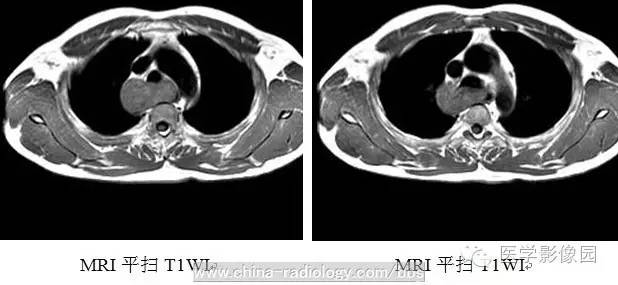

3、CT及磁共振(MRI)检查